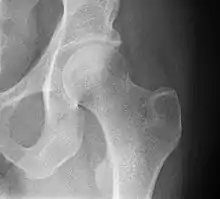

• Hip joint: AP and Lateral.[15]

• The Lauenstein projection a form of examination of the hip joint emphasizing the relationship of the femur to the acetabulum. The knee of the affected leg is flexed, and the thigh is drawn up to nearly a right angle. This is also called the frog-leg position.

Applications include X-ray of hip dysplasia.